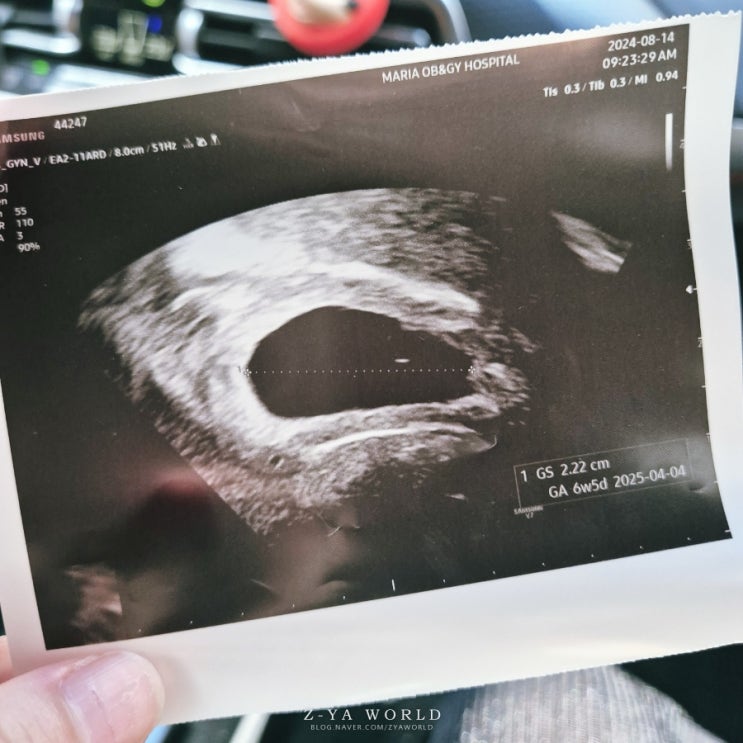

5일배양 2차 피검사 수치 아기집 확인 임신확인서